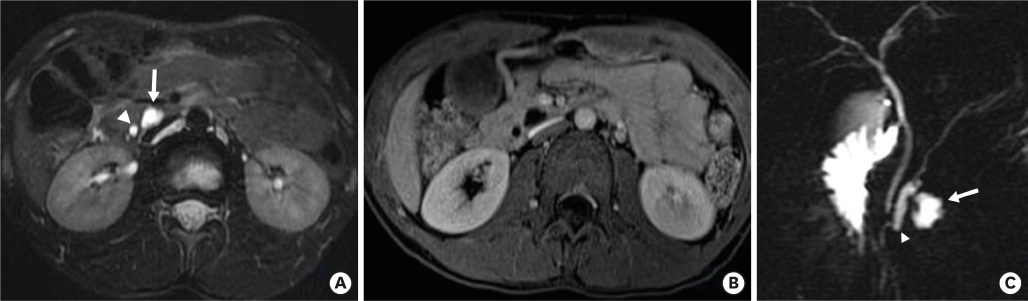

Fig. 3

(A) T2-weighted MRI reveals a small, lobulated cystic mass (arrow) in the pancreatic uncinate process. The adjacent pancreatic duct (arrowhead) is mildly dilated. (B) No solid enhancing components were revealed on T1-weighted MRI obtained after contrast administration. (C) Oblique-coronal, thick-slice magnetic resonance cholangiopancreatography reveals a lobulated cystic mass (arrow) and associated pancreatic duct dilatation (arrowhead).

MRI, magnetic resonance imaging.

The initial preoperative laboratory data revealed an elevated amylase of 153 U/L and a lipase level of 71 U/L. The liver function tests were otherwise normal except for an elevated alkaline phosphatase of 429 IU/L. Abdominal ultrasonography was performed, which showed a lobulated cystic mass in the pancreas (Fig. 1), and subsequent computerized tomography (CT) showed a mildly inflamed pancreas with a 1.2×0.9×1.3 cm-sized low-attenuating cystic lesion with a pleomorphic appearance at the pancreatic uncinate process (Fig. 2). A magnetic resonance imaging (MRI) scan performed later for cystic evaluation showed pancreatic ductal communication with the cystic lesion along with downstream ductal dilatation. Furthermore, mild dilatation of the main pancreatic duct was observed (Fig. 3). The cystic lesion revealed communication with the dorsal duct and congenital anomaly of the pancreatic duct, and pancreas divisum was suspected due to a lack of fusion of the ventral and dorsal ducts and the common bile duct, which joins with the dorsal duct. Therefore, given the suspicion of IPMN and symptoms of pancreatitis, the patient underwent a pylorus-preserving pancreaticoduodenectomy. The histopathology report revealed BD-IPMN with intermediate-grade dysplasia. The depth was limited to the pancreas without invasion of the surrounding adjacent organs. Pancreatic intraepithelial neoplasia was not applicable, and the mucinous glands were of the intestinal type (Fig. 4).